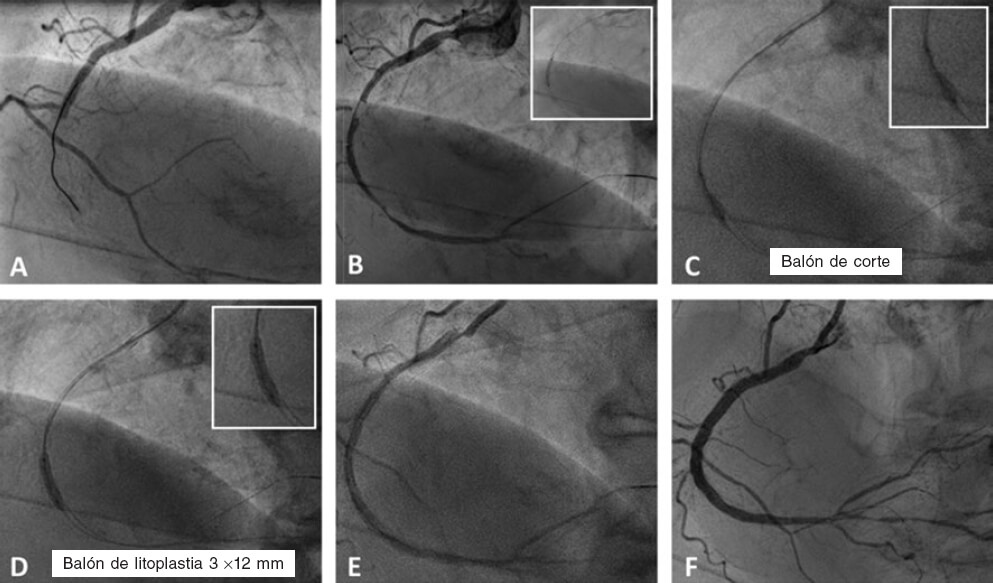

Figura 2. Caso de litoplastia coronaria en paciente con síndrome coronario agudo con elevación del segmento ST inferior. A: angiografía basal. B: resultado tras la predilatación con balón semidistensible de 2 × 15 mm. C: predilatación con balón no distensible de 2,5 × 8 mm y balón de corte de 2,5 × 6 mm sin éxito. D: litotricia coronaria con balón de litoplastia de 3 × 12 mm. E: resultado angiográfico tras la litoplastia coronaria. F: resultado final tras la implantación de dos stents farmacoactivos solapados (2,75 × 33 mm y 3 × 38 mm) y posdilatación con balón no distensible de 3 × 12 mm.

Indicaciones

La principal indicación de la LC son las lesiones calcificadas concéntricas con una distribución circunferencial del calcio41,42. Parece tener más efecto sobre el calcio más profundo que otras técnicas de modificación de la placa45-47. La LC es efectiva en vasos de gran calibre, pues existen balones de litoplastia de hasta 4 mm de diámetro. Este dispositivo se puede utilizar en lesiones bifurcadas, ya que permite situar 2 guías durante el procedimiento para proteger la rama lateral. Asimismo, el BL parece seguro y efectivo ante la presencia de tortuosidad significativa, reestenosis del stent debida a infraexpansión48,49 y lesión calcificada en el tronco común con disfunción ventricular izquierda grave50,51 (tabla 3). Otra indicación más discutible puede ser el tratamiento de LCGC en el contexto de un infarto agudo de miocardio con elevación del ST52 (figura 2).